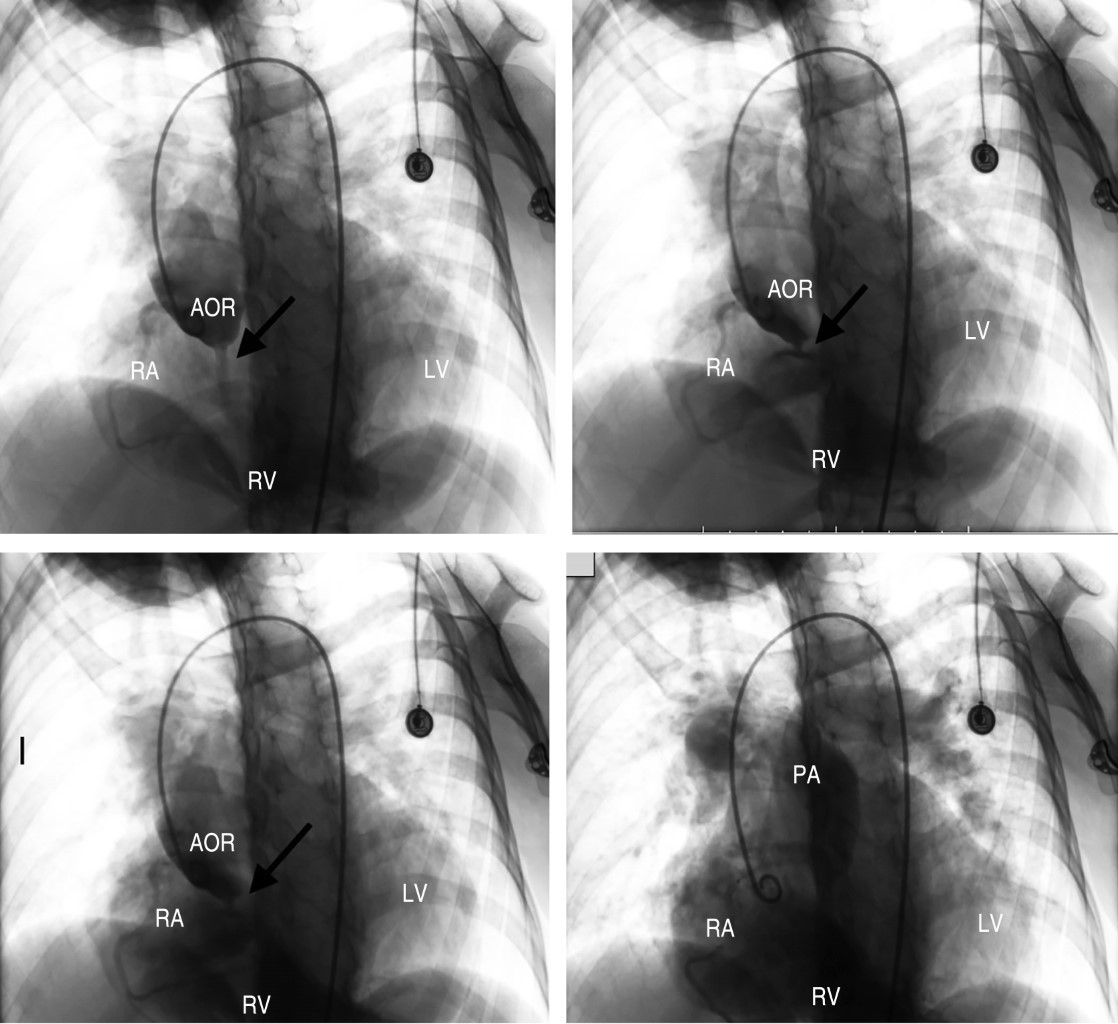

Fístula del seno coronario derecho por aneurisma roto hacia aurícula derecha en una paciente con síndrome de Noonan

Introducción: un aneurisma a nivel de los senos de Valsalva es una patología de origen congénito o adquirido. La presencia de fístulas, pueden así mismo, ser asintomáticas o expresarse a cualquier edad con distintas manifestaciones. Presentación del caso: paciente mujer de 34 años, portadora de síndrome de Noonan (SN); antecedente quirúrgico de cierre de comunicación interventricular. Desde los 27 años presenta episodios de disnea. La auscultación cardiopulmonar destaca la presencia de soplo continuo en segundo espacio intercostal paraesternal derecho. Se realiza ecocardiograma transtorácico con hallazgos de un aneurisma coronario derecho fistulizado. Se llevó a cabo cirugía donde se observa fístula de seno coronario derecho a aurícula derecha, procediendo a cierre. Conclusiones: una fístula de un seno coronario hacia una cavidad cardíaca es una presentación poco frecuente de un aneurisma roto, por lo que destaca la presentación de esta patología en una paciente con una RASopatia relacionada con defectos cardíacos. El diagnóstico requiere un adecuado abordaje. Sin embargo, en algunos casos, la localización exacta del defecto se consigue en la cirugía. Su diagnóstico y tratamiento temprano es crucial.

Figura 1

Figura 2

Figura 3

Figura 4